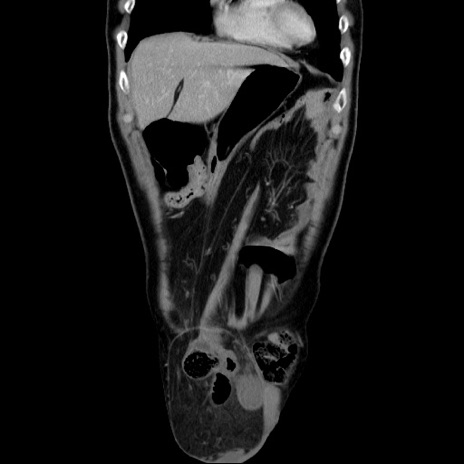

症例34(冠状断像)

【症例】60歳代 男性

【主訴】右鼠径部膨隆

【現病歴】1年程前より右鼠径部膨隆あり。自己にて還納可能だったため放置していた。3時間前より右鼠径部の脱出を認め、還納困難となり受診。

【既往歴】高血圧

【身体所見】右鼠径部に小児頭大の膨隆あり。弾性硬であり、用手還納は困難。左鼠径部にも膨隆を認める。脱出はなし。